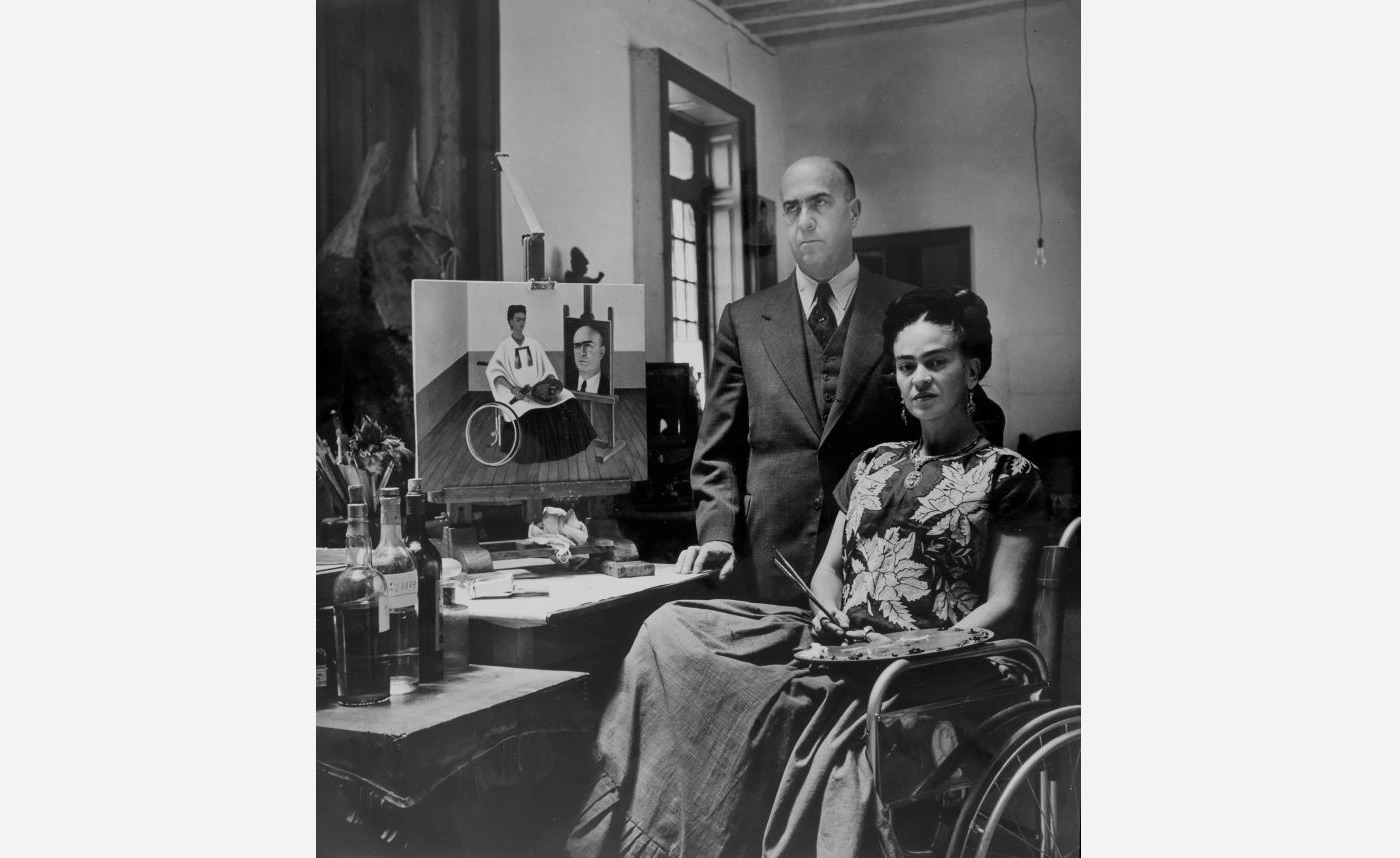

Her Doctors

Suffering from chronic pain and lifelong injuries, Frida Kahlo encountered many doctors, each attempting to provide a medical solution to her health complications. Having undergone over 30 medical procedures, she spent long periods in hospital, eventually developing close relationships with her doctors. She often confided in them, writing personal letters asking for their opinion on her private life—including her marriage—and even painted self-portraits dedicated to them. These doctors were both trusted medical advisors and emotional supports to Frida.Featured artworks

Gisèle Freund, Frida Kahlo and Dr. Juan Farill with her Self-Portrait, 1951. © Gisele Freund/IMEC/fonds MCC

Gisèle Freund, Frida Kahlo and Dr. Juan Farill with her Self-Portrait, 1951. © Gisele Freund/IMEC/fonds MCC -